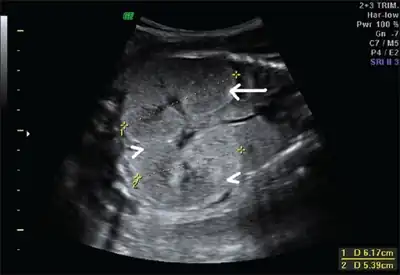

Ultrasonography is the primary method to evaluate autosomal recessive polycystic kidney disease, particularly in the perinatal and neonatal stages.[3]

- Fetus with bilateral enlarged/hyperechogenic kidneys arrow & diminished cortico-medullary differentiation arrowhead